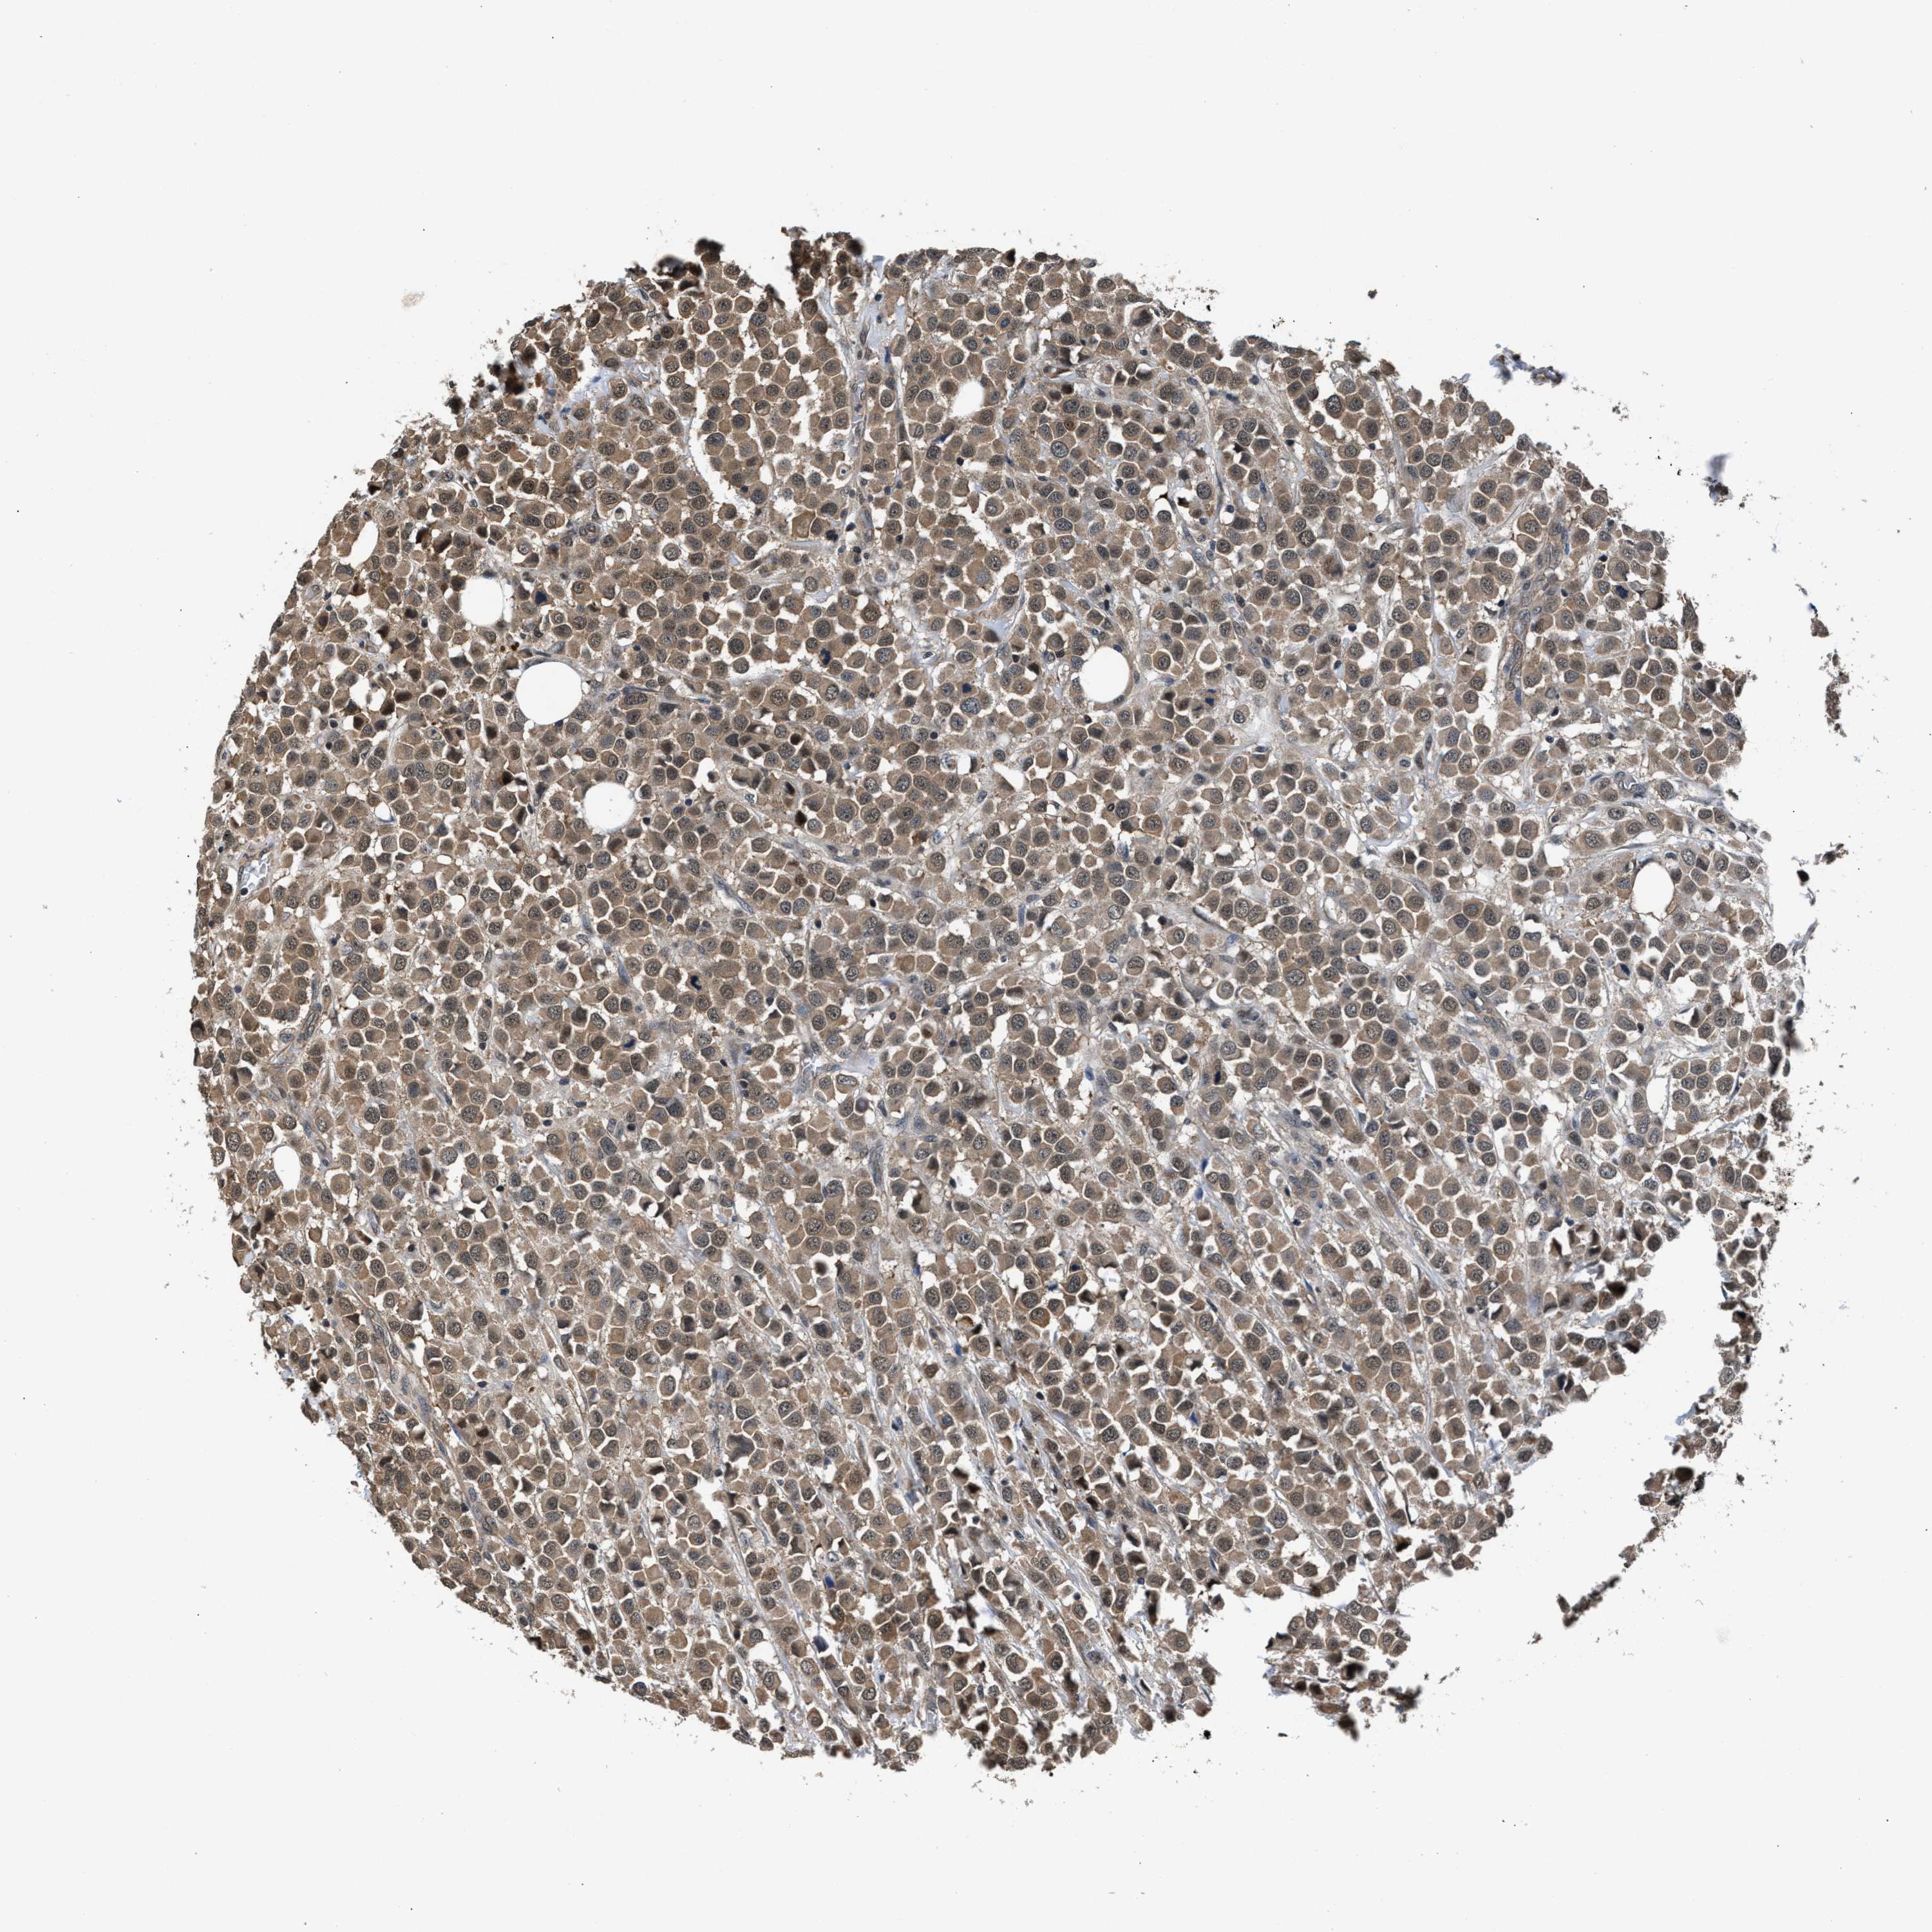

CANCER BREAST CANCER Show tissue menu

BRCA TCGA BRCA VALIDATION PROTEIN EXPRESSION